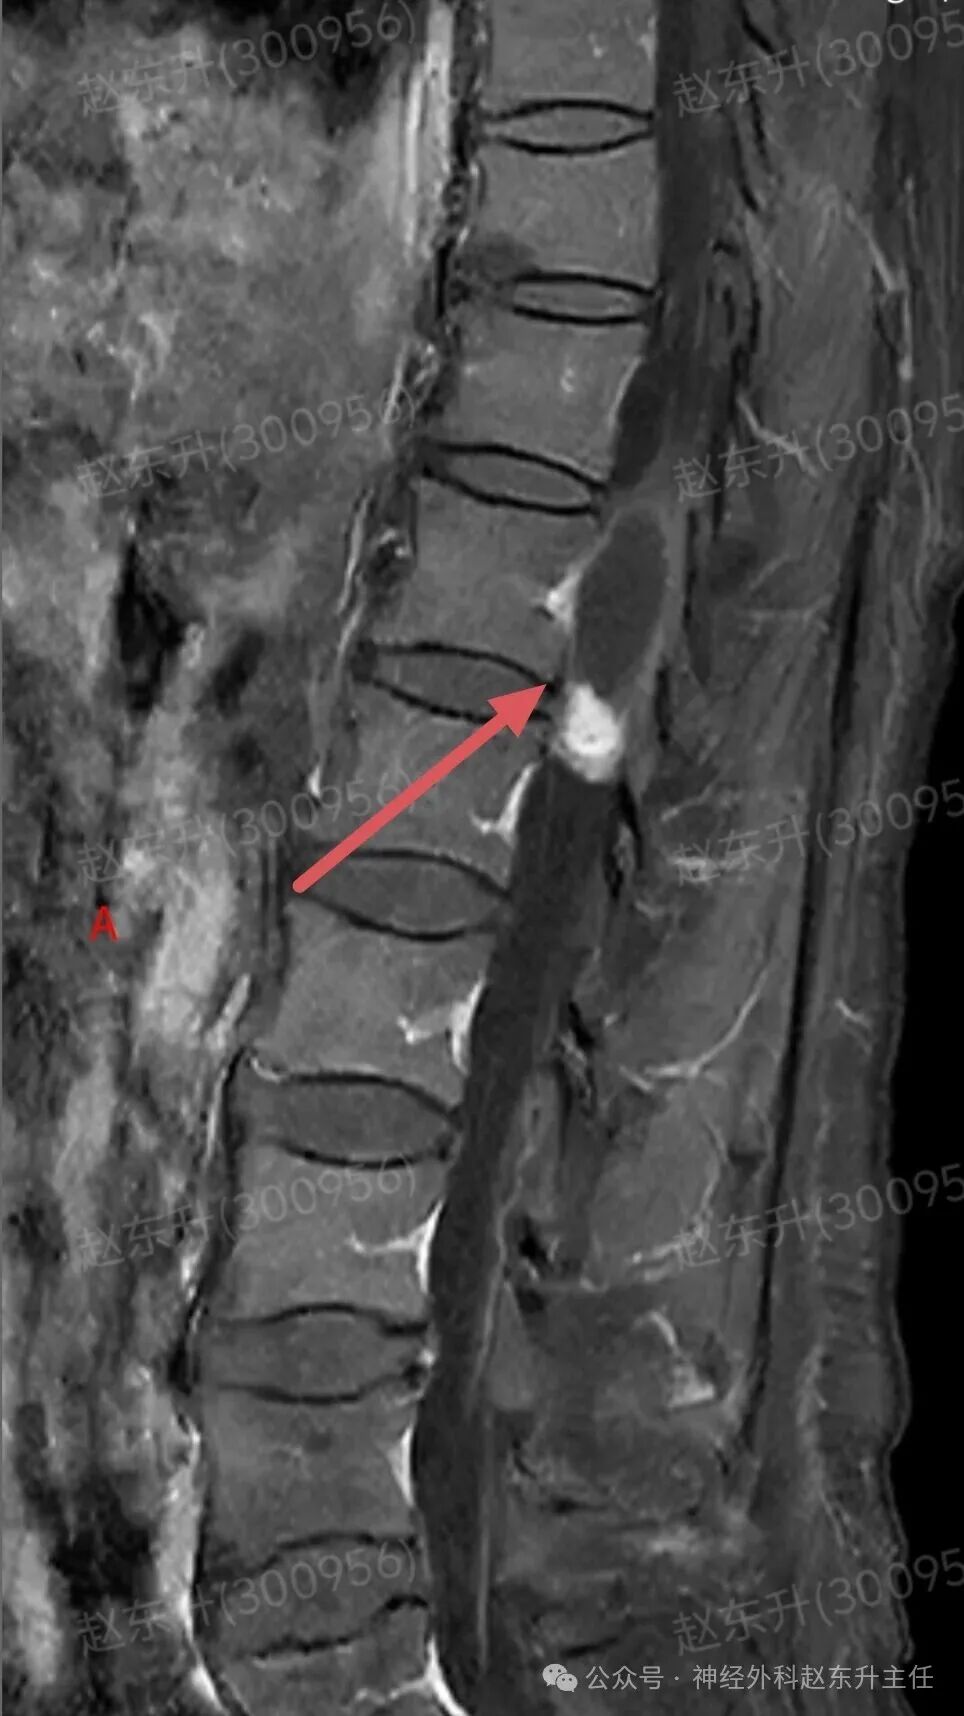

上周门诊来了一位58岁女性,患者因为下肢和腰背部顽固性疼痛半年,在各大医院就诊曾行针灸按摩,艾灸电疗等治疗没见缓解,而且疼痛评分可以达到8-9分,口服止痛药无效,康复理疗无效。随后查了一下腰椎磁共振,发现胸12腰1节段脊髓内异常信号,随后收入我科。入院之后查肌电图提示下肢和骶神经损伤严重,随后我们在全麻下使用显微镜,并且术中电生理监测下,给予脊髓内肿瘤次全切除,术后病理提示是胶质瘤。术后第2天我们就给他用了经颅磁刺激等神经康复治疗,虽然术后第1天右下肢肌力较术前减退,但经过10天的治疗以后,下肢肌力逐渐恢复,可以下地行走了。术后他还需要进一步的放疗和化疗来抑制肿瘤的生长,预防肿瘤复发。

图片图片图片图片图片图片图片图片切除的肿瘤图片术后病理西安市红会医院神经外科赵东升主任介绍:脊髓内胶质瘤是一种起源于脊髓实质内部的胶质细胞(即神经系统的“支持”细胞)的肿瘤。与脊膜瘤(位于脊髓外)的关键区别在于,它生长在脊髓内部,因此会浸润并破坏正常的脊髓神经组织核心特征:性质:涵盖从低级别良性到高级别恶性的完整谱系,但以低级别为主。位置:完全位于脊髓中央,可累及多个脊髓节段,甚至全长脊髓。特点:肿瘤与正常脊髓组织边界不清(浸润性生长),手术全切极为困难。其生长直接破坏神经传导束,导致严重神经功能障碍。发病率:相对少见,约占所有中枢神经系统胶质瘤的2-4%,但却是儿童最常见的髓内肿瘤。无明显性别差异。与脊膜瘤的关键区别总结

主要类型1.室管膜瘤(约占60%):常见的成人髓内胶质瘤。多为低级别(WHO I级和II级),生长缓慢。常发生于颈段和胸段,常有明确边界,有时可有“假包膜”,是手术全切希望最大的一种。2.星形细胞瘤(约占30%):常见的儿童髓内胶质瘤。从低级别(毛细胞型星形细胞瘤,WHO I级,预后好)到高级别(胶质母细胞瘤,WHO IV级,预后极差)都有。浸润性生长为特点,与正常脊髓几乎无边界,手术全切风险极高。3.其他少见类型:如血管母细胞瘤(常与VHL病相关)、少突胶质细胞瘤等。临床表现(症状)症状因肿瘤生长缓慢而隐匿、渐进性加重,早期易被忽视。典型症状:1.感觉障碍(最早、最常见):l分离性感觉障碍:这是特征性表现。由于肿瘤侵犯脊髓中央的白质前连合,导致痛觉、温觉纤维受损,而触觉、深感觉保留。患者表现为双侧对称性的、节段性的痛温觉减退或消失,而触觉正常l麻木、酸痛、束带感。2.运动障碍:n肿瘤平面以下出现肢体无力、僵硬、肌肉萎缩(尤以手部小肌肉萎缩常见)。n行走困难,步态不稳。3.疼痛:定位不明确的颈背部疼痛,夜间痛可能更明显。4.自主神经功能障碍(晚期):l大小便失禁或困难。l性功能障碍。l皮肤营养障碍(无汗、皮肤干燥等)。诊断增强磁共振(MRI): 是首选和确诊的关键检查。典型表现:可见脊髓呈梭形、偏心性或中心性增粗。肿瘤在T1像呈等或低信号,T2像呈高信号,增强后强化模式多样(可均匀、不均匀或环形强化)。可清晰显示肿瘤范围、有无囊变、脊髓空洞等。CT:价值有限,主要用于评估是否有脊椎骨质改变。治疗治疗远比脊膜瘤复杂,需在多学科团队(神经外科、肿瘤科、放疗科)指导下进行个体化综合治疗手术治疗(首要且核心):l目标:在最大限度保护神经功能的前提下,实现最大安全程度的肿瘤切除。全切是目标,但常因肿瘤边界不清而无法实现。l技术:在术中神经电生理监测(监测运动、感觉传导束功能)的保驾护航下,使用显微外科技术、超声吸引、激光等进行精细操作。功能保护优先于肿瘤全切放射治疗:主要适用于:高级别胶质瘤术后辅助治疗、无法全切的低级别胶质瘤术后残留、肿瘤复发无法再次手术者。化学治疗:l对于高级别(恶性)脊髓胶质瘤,可参照脑胶质瘤方案进行化疗(如替莫唑胺)。l对于部分复发的低级别胶质瘤也可能使用。预后与随访预后差异巨大,高度依赖于肿瘤的病理类型和分级l低级别室管膜瘤:若能实现全切,预后良好,可达到长期无进展生存,甚至临床治愈。复发率低。l低级别星形细胞瘤(如毛细胞型):全切后预后也很好。次全切后也可能长期稳定。l高级别胶质瘤(如胶质母细胞瘤)预后极差,即使积极治疗,也极易在脊髓内播散复发,生存期短。l随访:术后需定期(通常每3-6个月,后逐渐延长)进行增强MRI复查,监测肿瘤是否残留或复发。神经功能康复治疗至关重要赵东升主任简介医学硕士,西安市红会医院北院区神经外科主任医师,从事神经外科近20年。使用独创的“三维一体疗法”成功促醒大量昏迷病人,使上百例脊髓损伤瘫痪患者重新站起来。最早在陕西省开展第一例脊髓电刺激治疗昏迷病人,第一例脊髓电刺激手术治疗截瘫病人,第一例脊髓电刺激手术治疗下肢缺血顽固性疼痛。主编专著3部,参编专著11部,发表学术论文30余篇,荣获国家专利32项(其中四项发明专利),担任多部杂志编委及审稿专家。擅长:1.脑病方面:昏迷促醒,脑肿瘤、脑积水、脑梗死偏瘫、肌张力增高、顽固性癫痫、三叉神经痛、脑干出血、老年痴呆、帕金森、头痛等;2.脊髓病方面:脊髓损伤、脊柱术后疼痛、大小便障碍、脊髓肿瘤、脊髓空洞、小脑扁桃体下疝畸形、脊髓栓系、脊膜膨出、痉挛性截瘫等;3.周围神经疾病方面:糖尿病足、下肢缺血性疼痛、臂丛神经损伤、腓总神经损伤、腕管综合征、肘管综合征、男性功能障碍等门诊时间:北院区:周一全天门诊二楼203A  第五诊室南院区:周二全天门诊三楼310诊室